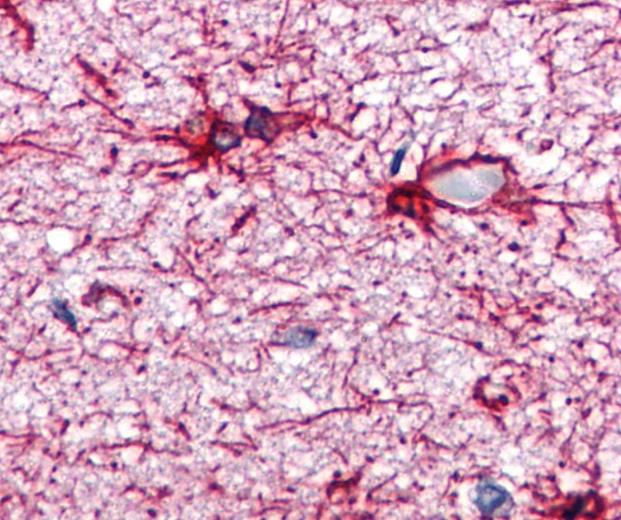

The mouse monoclonal antibody GA-5 reacts with GFAP, the principal marker of astroglial cells in the central nervous system, which is specifically expressed in satellite cells in peripheral ganglia and in non myelinating Schwann cells in peripheral nerves. The GFAP protein runs on gels at ~55 kDa protein, usually associated with lower Mw bands which are thought to be proteolytic fragments and alternate transcripts from the single gene.

GFAP (glial fibrillary acidic protein) was discovered by Bignami et al. (1972) as a major fibrous protein of multiple sclerosis plaques. It was subsequently found to be a member of the 10 nm or intermediate filament protein family, specifically the intermediate filament protein family class III, which also includes peripherin, desmin and vimentin. GFAP is heavily, and specifically, expressed in astrocytes and certain other astroglia in the central nervous system, in satellite cells in peripheral ganglia, and in non-myelinating Schwann cells in peripheral nerves. In addition, neural stem cells frequently strongly express GFAP. It is also found in the lens epithelium, Kupffer cells of the liver, in some cells in salivary tumors and has been reported in erythrocytes. Although its function is not fully understood, GFAP protein is probably involved in controlling the shape and movement of astrocytes. The protein probably also plays a significant role in the interactions of astrocytes with other cells, which are required for the formation and maintenance of the insulating layer (myelin) that covers nerve cells. Additionally, GFAP protein may assist in maintaining the protective barrier that allows only certain substances to pass between blood vessels and the brain (blood-brain barrier).In adults, GFAP levels increase as a result of the proliferation of astrocytes that occurs in a response to a variety of physical, chemical and etiological insults, including Alzheimer’s disease, epilepsy and multiple sclerosis.Antibodies to GFAP are therefore very useful as markers of astrocytic cells and neural stem cells and for distinguishing of neoplasms of astrocytic origin from other neoplasms in the central nervous system. Finally, Alexander's disease was recently shown to be caused by point mutations in protein coding region of the GFAP gene (Brenner et al., 2001). All forms of Alexander disease are characterized by the presence of Rosenthal fibers, which are GFAP containing cytoplasmic inclusions found in astrocytes.

Immunohistochemistry staining of human brain cortex (paraffin sections) using anti-GFAP (GA-5). Commercially tested by LifeSpan BioSciences.